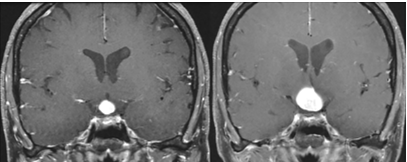

Una mujer de 35 años con 2 hijos presentó una historia de 2 años de amenorrea, poliuria (5-10 L/día) -polidipsia (mayor de 5 L/día) y aumento de peso. La historia clínica mostró que la paciente tuvo su último parto cuando tenía 30 años y estuvo lactando y tuvo menstruaciones regulares hasta 2 años antes. En el examen físico el examen del campo visual no reveló ninguna anomalía. La investigación hormonal y bioquímica basal mostró hiperprolactinemia; IGF-1 disminuida, hipotiroidismo central con ATPO neg; hipogonadismo central; hipoadrenalismo central y densidad urinaria de 1,005 (1,015-1,025). La investigación inmunológica reveló la presencia de anticuerpos antihipotalámicos (AHA) en títulos elevados; 1/128 (normal, Ë1/8), dirigido contra células secretoras de arginina vasopresina (AVP). Los anticuerpos antipituitarios (APA) fueron negativos. La resonancia magnética (IRM) mostró una lesión levemente hipointensa en el hipotálamo y con falta del punto brillante de neurohipófisis. La lesión era levemente hiperintensa en las imágenes potenciadas en T2 con un realce heterogéneo en T1 con contraste. Las dimensiones máximas A-P, transversal y craneocaudal de la lesión se midieron como 8 Ã 11 Ã 10 mm, respectivamente.

La paciente fue reevaluada 3 meses después y se detectó una progresión en el tamaño de la lesión con lo que se planificó la resección microneuroquirúrgica.

RMN al diagnóstico y a los 3 meses

La hipotalamitis no posee características específicas en la resonancia magnética para distinguirla de otras patologías supraselares como gliomas, metástasis y encefalitis. Hay leve hipo o isointensidad en T1 e hiperintensidad leve en T2 con respecto a la sustancia blanca normal, y estas son características comunes para la mayoría de las patologías hipotalámicas. La falta de brillo de la neurohipófisis en T1 se encontró tanto en el caso actual como en la mayoría de los estudios previos. Aunque el tallo infundibular tiene un grosor normal, la ausencia de una señal T1 alta de la neurohipófisis probablemente se deba a la interrupción entre la neurohipófisis y el hipotálamo. El grosor del tallo hipofisario se encuentra aumentado en algunos estudios previos, pero generalmente sigue siendo de tamaño normal como en el caso actual. El realce heterogéneo de orientación periférica con o sin edema del quiasma óptico o del tracto es un hallazgo común. Una combinación de características de resonancia magnética con la hiperdensidad de la tomografía computarizada es extremadamente útil para el diagnóstico preciso de hipotalamitis. Además de las características inmunohistoquímicas, la resonancia magnética de nuestro caso no mostró indicios de inflamación hipofisaria que se extendiera a la región hipotalámica.